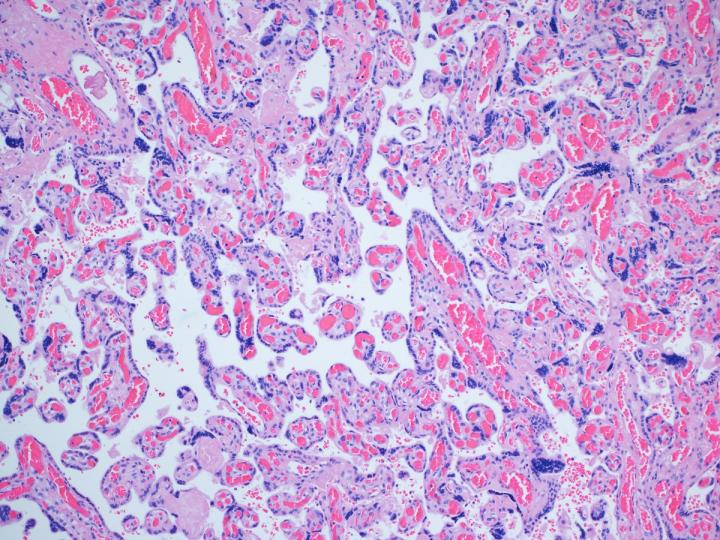

image: A microscopic look at a placenta in the study, which was not damaged from the COVID-19 vaccine.

CHICAGO --- A new Northwestern Medicine study of placentas from patients who received the COVID-19 vaccine during pregnancy found no evidence of injury, adding to the growing literature that COVID-19 vaccines are safe in pregnancy.

"The placenta is like the black box in an airplane. If something goes wrong with a pregnancy, we usually see changes in the placenta that can help us figure out what happened," said corresponding author Dr. Jeffery Goldstein, assistant professor of pathology at Northwestern University Feinberg School of Medicine and a Northwestern Medicine pathologist. "From what we can tell, the COVID vaccine does not damage the placenta."

The study authors collected placentas from 84 vaccinated patients and 116 unvaccinated patients who delivered at Prentice Women's Hospital in Chicago and pathologically examined the placentas whole and microscopically following birth. Most patients received vaccines - either Moderna or Pfizer - during their third trimester.

The scientists also looked for abnormal blood flow between the mother and fetus and problems with fetal blood flow - both of which have been reported in pregnant patients who have tested positive for COVID.

The rate of these injuries was the same in the vaccinated patients as for control patients, Goldstein said. The scientists also examined the placentas for chronic histiocytic intervillositis, a complication that can happen if the placenta is infected, in this case, by SARS-CoV-2. Although this study did not find any cases in vaccinated patients, it's a very rare condition that requires a larger sample size (1,000 patients) to differentiate between vaccinated and unvaccinated patients.